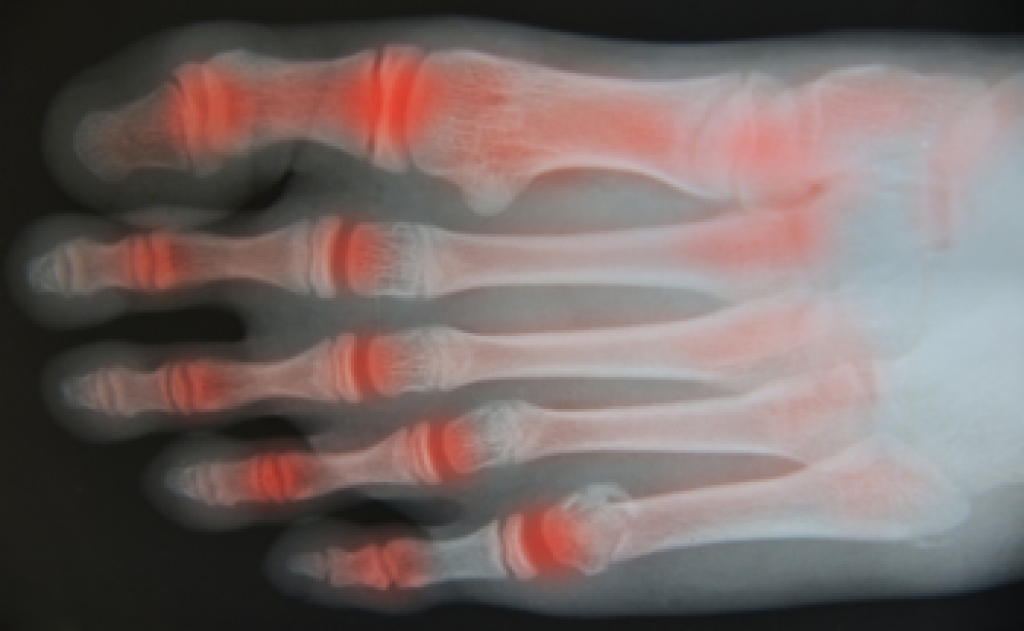

Osteoarthritis is a degenerative joint condition that occurs when cartilage wears down over time, leading to pain and stiffness. In the feet, it often affects joints in the toes and midfoot, making walking uncomfortable. Causes include aging, excess body weight, genetic predisposition, and other forms of arthritis that contribute to joint damage. Symptoms include pain, swelling in foot joints, reduced flexibility, and discomfort that may worsen at night. Persistent foot pain can interfere with daily activities and overall quality of life. A podiatrist can diagnose the condition, recommend supportive footwear, provide custom orthotics, and develop a treatment plan to reduce pain and improve mobility. If you are experiencing ongoing foot discomfort or swelling, it is suggested that you consult a podiatrist who can offer effective relief and management solutions.

Arthritis is a joint disorder that involves the inflammation of different joints in your body, such as those in your feet. Arthritis is often caused by a degenerative joint disease and causes mild to severe pain in all affected areas. In addition to this, swelling and stiffness in the affected joints can also be a common symptom of arthritis.